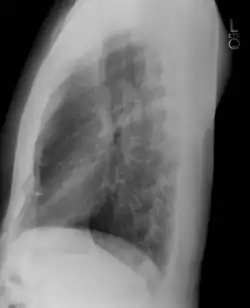

Las vistas laterales son obtenidas de una manera similar a las vistas posteroanteriores, excepto que en la vista lateral el paciente se para con ambos brazos levantados y el lado izquierdo del tórax apretado contra una superficie plana.

Placa lateral de tórax en el sujeto normal. El lado izquierdo del tórax se apoya sobre el cassette de la película radiográfica para impedir la magnificación del corazón. Las placas posteroanterior y lateral constituyen el "par radiográfico de tórax". -